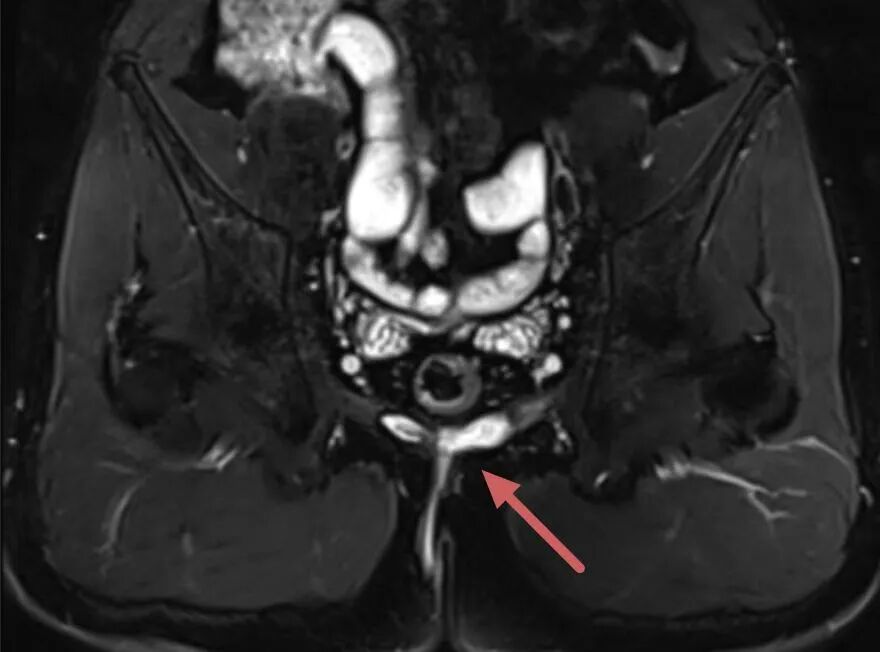

精准诊断:构建手术的“高清导航地图” 复杂性肛瘘治疗的最大难点在于瘘管走向复杂、位置深,传统检查难以看清全貌,如同在迷雾中手术,极易导致治疗不彻底或损伤肛门功能。我院肛肠科的技术突破,始于诊断环节的革新,采用 “双影像精准定位”技术,为每位复杂肛瘘患者定制手术蓝图: ·盆腔磁共振成像(MRI):已成为评估复杂性肛瘘的金标准。我院影像科与肛肠科紧密协作,针对肛瘘特点优化扫描序列。能三维立体显示瘘管的主干、分支、内口(感染源头)及其与肛门控便肌肉群的精确关系。这是制定安全、有效手术方案的基石。 · 肛周超声:则像灵活的“实时雷达”,可在术前或术中动态观察,对关键部位进行精确定位,与MRI形成完美互补。 “MRI+超声”的融合诊断模式, 为外科医生构建了覆盖术前全局规划与术中实时调整的“双保险”导航系统,确保了手术靶向的绝对精准,从源头奠定了成功的基础。 术式革新:在根治与功能保护间找到完美平衡 基于精准的影像诊断,针对吴先生这种复杂病例,肛肠科团队成功实施了“分段开窗旷置术”结合“括约肌间切开并保留括约肌挂线术”的复合术式。肛肠科刘安乐副主任医师介绍,该手术方案通过术前精准影像定位,术中先对瘘管复杂分支进行分段开窗引流,清除坏死组织,再对主瘘管采用保留括约肌挂线术,利用挂线的慢性切割作用,避免一次性切断括约肌导致肛门失禁,同时促进创面愈合。这种术式既解决了复杂瘘管引流不畅的问题,又最大程度保护了肛门括约肌功能,从根源上降低复发风险。 无痛病房建设:让康复之路温暖而从容 技术的突破不仅体现在手术室,更贯穿于围手术期的全程。市二院肛肠科着力打造的“无痛病房”是现代快速康复外科(ERAS)理念的生动实践,旨在彻底改变患者对肛肠手术“剧痛难忍”的传统恐惧。 为吴先生建立的多模式镇痛体系是一套预防性、个体化、多途径的镇痛方案: *术前预防镇痛:在手术开始前,通过疼痛教育、心理疏导联合超前镇痛药物,降低中枢神经敏感度,从源头上减轻术后疼痛。 * 术中长效麻醉:术中在手术创面区域进行药物性神经阻滞术,使术后创面无痛化持续时间达到一周以上。 *中医技术赋能:穴位贴敷、中药栓剂纳肛、肛门中药熏洗坐浴、红光照射等物理疗法,明显缓解疼痛,促进创面愈合。 在本病例中,患者术后疼痛VAS评分始终控制在3分(轻度疼痛)以下,确保了其良好的睡眠、饮食与早期下床活动。舒适的体验直接促进了康复。患者能够配合每日必要的坐浴和换药,营养摄入充足,循环呼吸功能良好,伤口在最佳状态下愈合,形成了“镇痛佳→恢复快→痛苦少”的良性循环。经过一个多月的悉心治疗与护理,张先生的创面完全愈合,肛门功能恢复正常,近期复查未发现任何复发迹象。 肛肠科通过此例多次复发的复杂性高位肛瘘的成功治愈,系统性地展示了科室在 “精准诊疗体系”与 “舒适医疗体系” 建设上的双重突破。我们将继续以此为契机,深耕肛肠疾病领域,特别是疑难复杂性肛瘘的诊疗,以更精准的刀、更温暖的术、更无痛的康复,守护每一位患者的健康与尊严。